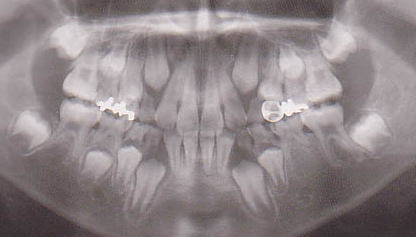

| 乳歯は、それぞれの年齢で重要な役割を果たしています。 そして、ある時期が来ると下から萌出してくる永久歯と交換します。 もし、交換すべき時期より虫歯が原因で早く喪失してしまったらどうなるでしょうか。 例えば、下の写真(図1)を見て下さい。永久歯が歯と歯との間にはさまれて出てこれなくなっています。 また、図の2のように、乳歯は、下から萌出してくる永久歯の場所を確保している役割を果たしています。 どうせ永久歯と交換するから虫歯になっても関係ないと考えるのは大きな間違いです。 乳臼歯は、10歳頃に永久歯と交換します。もし、虫歯でもっと早い時期に喪失すればほとんどの場合下の図1の写真のような状況を引き起こします。 そして大人になっても同じ状況が続きます。周囲に食べかすが溜まりやすく虫歯や歯周病になり、不正な萌出をした歯やその周囲の歯が失われていく可能性が高くなります。ブリッジや入れ歯が必要になります。ブリッジならその周囲の歯を削ることになり、削った歯は、削らない歯より寿命が短くなります。入れ歯も同様です。また、治療をしないでそのままにしておくと図の3のように歯が移動してかみ合わせが悪くなり、歯列不正や顎関節症など様々な問題を引き起こします。そういう悪循環で歯がどんどん失われていくことになります。図4 御理解いただけたでしょうか? たかが、乳歯と思わないで下さい。 |